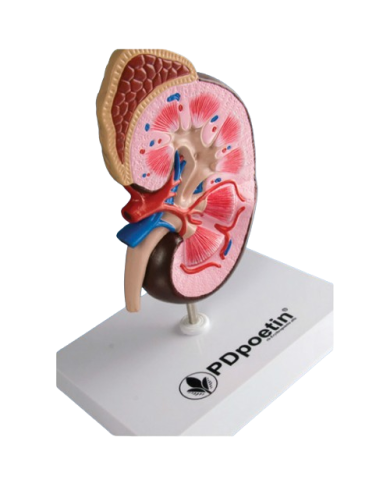

Modello anatomico PER FORNITURE CASE FARMACEUTICHE

Modello anatomico PER FORNITURE CASE FARMACEUTICHE

Modello anatomico PER FORNITURE CASE FARMACEUTICHE

Modello anatomico PER FORNITURE CASE FARMACEUTICHE

Modello anatomico PER FORNITURE CASE FARMACEUTICHE

Modello anatomico PER FORNITURE CASE FARMACEUTICHE

Modello anatomico PER FORNITURE CASE FARMACEUTICHE

Modello anatomico PER FORNITURE CASE FARMACEUTICHE

Modello anatomico PER FORNITURE CASE FARMACEUTICHE

Modello anatomico PER FORNITURE CASE FARMACEUTICHE

Modello anatomico PER FORNITURE CASE FARMACEUTICHE

Modello anatomico PER FORNITURE CASE FARMACEUTICHE

Modello anatomico PER FORNITURE CASE FARMACEUTICHE

Modello anatomico PER FORNITURE CASE FARMACEUTICHE

Modello anatomico PER FORNITURE CASE FARMACEUTICHE

Modello anatomico PER FORNITURE CASE FARMACEUTICHE

Modello anatomico PER FORNITURE CASE FARMACEUTICHE

Modello anatomico PER FORNITURE CASE FARMACEUTICHE

Modello anatomico PER FORNITURE CASE FARMACEUTICHE

Modello anatomico PER FORNITURE CASE FARMACEUTICHE

Modello anatomico PER FORNITURE CASE FARMACEUTICHE

Modello anatomico PER FORNITURE CASE FARMACEUTICHE